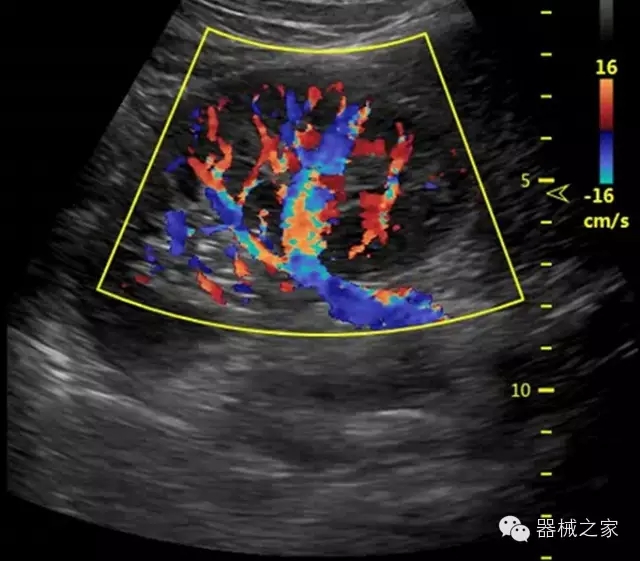

臨床圖片賞析

產(chǎn)品特點(diǎn)

·獨(dú)有的RF平臺提高微小細(xì)節(jié)顯示、圖像對比度和邊界清晰度;

·特有的XCEN探頭,超寬的帶寬,表現(xiàn)更高分辨率和對比度;

·單晶純凈波探頭提供更佳的穿透力和彩色敏感度;

·完整的3D/4D臨床應(yīng)用,STIC, MCUT 和Auto NT等滿足產(chǎn)科所有應(yīng)用;

·更高的HQ羊膜腔鏡成像技術(shù)精細(xì)觀察每一個暗區(qū)細(xì)節(jié);

·智能的觸摸屏界面,能任意角度方位旋轉(zhuǎn)3D圖像,以及注釋快速標(biāo)記,提供直觀與便捷的操作,提高了工作效率;

介入室/手術(shù)室

·Needle Enhancement 穿刺增強(qiáng)技術(shù),清晰顯示穿刺針尖,定位目標(biāo)精確穿刺;

·智能的聲控功能,以及全屏顯示真正意義上解決醫(yī)生術(shù)中應(yīng)用;

Xcen探頭技術(shù)

·獨(dú)有的Xcen高頻18MHz探頭,使微小病灶的顯示成為現(xiàn)實(shí),為臨床提供了更廣泛的臨床應(yīng)用;

·Xcen超寬頻帶探頭技術(shù)比常規(guī)探頭頻寬提高了30%,具有更廣泛的臨床應(yīng)用,更高的頻率讓我們獲得了更好的細(xì)微分辨率和對比度的圖像;

肌骨理療

·智能感知組織特異性的VTissue技術(shù),結(jié)合特有高達(dá)22MHzXcen線陣探頭, 以及獨(dú)有敏感的RF射頻血流提供了優(yōu)異臨床圖像;

·智能的教學(xué)操作流程提供全面及專業(yè)的操作步驟指導(dǎo),便捷藍(lán)牙傳輸保障信息流暢;

便捷傳輸功能

·藍(lán)牙傳輸/ WIFI 郵件/ 移動網(wǎng)絡(luò)/ DICOM;

·ICU/CCU;

·飛依諾特有心臟純凈波探頭提供更好的穿透力和彩色敏感度,以及結(jié)合TView梯形拓展改善困難病人深部組織成像;

·獨(dú)有RF敏感血流使得心臟血流完美呈現(xiàn);